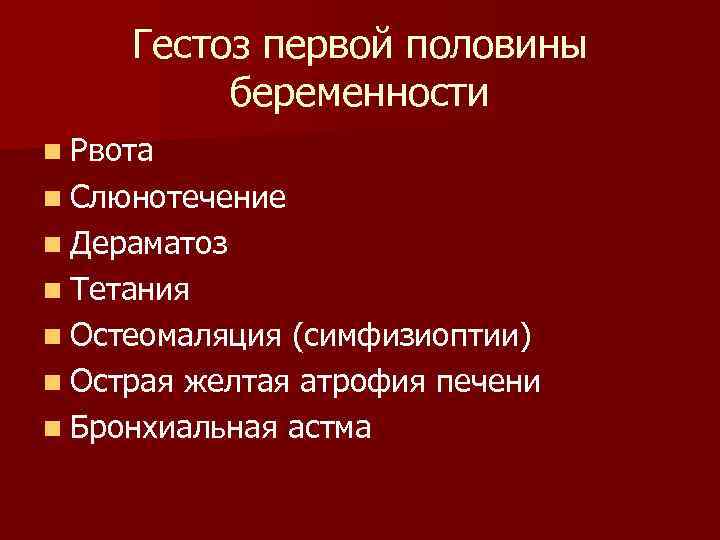

Гестоз первой половины беременности n Рвота n Слюнотечение n Дераматоз n Тетания n Остеомаляция (симфизиоптии) n Острая желтая атрофия печени n Бронхиальная астма

Гестоз первой половины беременности n Рвота n Слюнотечение n Дераматоз n Тетания n Остеомаляция (симфизиоптии) n Острая желтая атрофия печени n Бронхиальная астма